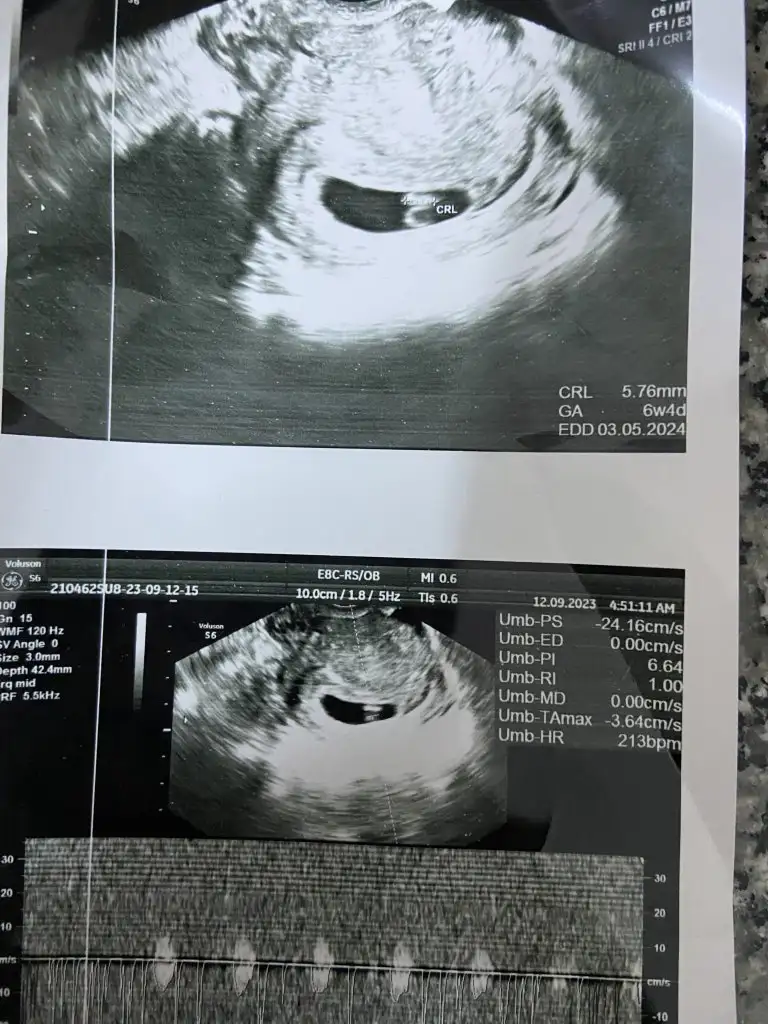

MerhabaBenim ultrasonumuda yorumlarmısınız rica etsem

6 hafta 5 günlük atacağım görselMerhaba

Başka resim yok elimde6 hafta 5 günlük atacağım görsel